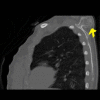

Osteochondromas commonly affect the proximal humerus, pelvis, and knee but are rarely seen on flat bones. Herein, we present the case of a 15-year-old female patient with osteochondroma located at the dorsal aspect of the scapula. The patient was admitted to the Orthopedics and Traumatology Department with the complaint of a mass on the left upper back for five years. The patient complained of the inability to sleep in the supine position, pain with shoulder motion, and cosmetic discomfort for two years. X-rays of the left shoulder revealed a bony mass arising from the dorsal aspect of the left scapula. The patient underwent an operation, and a specimen was sent for histopathologic examination. The histopathologic investigation confirmed the diagnosis of non-malignant transformation osteochondroma. While osteochondroma is not common in the scapula, it should be kept in mind that the most common benign tumor of the scapula is osteochondroma.